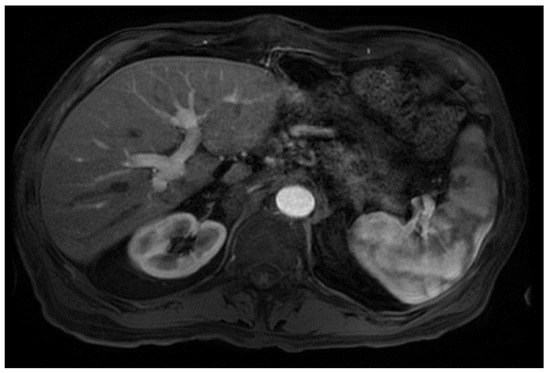

From a radiological perspective, the imaging plays a role in HCC diagnosis by detecting lesions, stratifying them based on standardized imaging features (LI-RADS), and providing staging information. Imaging also guides treatment by evaluating response to therapy or identifying the spread of disease; our patient had no postoperative complications or graft rejection. At his around 1-year post-transplant follow-up the patient continues to be in good health with a stable graft and no signs of cancer recurrence (Figure 4).

Figure 4.

Magnetic resonance imaging of the abdomen. T1 with contrast, orthotopic liver transplant has been successfully achieved, no mass, and the impression is normal (captured at the post-transplant follow-up visit).